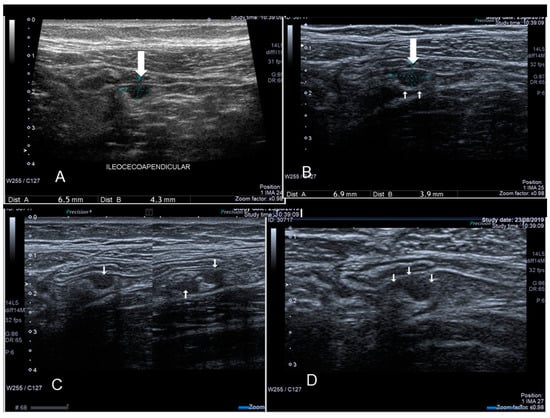

3.1. Endometriosis of the Appendix

The appendix is also an unusual site of extra-pelvic endometriosis. Endometriotic lesions affecting this area may be asymptomatic or may provoke acute appendicitis, melena, ruptured bowel or obstructed bowel from intussusception. Appendiceal endometriosis has a typical histopathological appearance: the mucosa is always left unscathed while the endometrial glands, stroma and hemorrhagic foci are gathered in the muscular and seromuscular layers [24]. Appendiceal endometriosis may have similarities with the clinical presentation of diverticular disease, colorectal cancer, inflammatory bowel disease, carcinoid tumors, benign intramural neoplasms, occult intra-abdominal metastases, mesenteric neoplasms and pelvic abscesses [25]. In ultrasonography appendiceal endometriosis is characterized by a solid lesion in the wall of small bowel, usually well defined (Figure 12, Figure 13, Figure 14 and Figure 15).

Figure 12. Sonographic features of an endometriotic nodule of cecum (see white arrow) (A) and appendix (see white arrow) (B).

Diagnostics 10 00345 g012

Figure 13. Endometriosis of appendix (see thin and thick white arrow) confirmed at surgery (AD).

Diagnostics 10 00345 g013

Figure 14. Endometriosis of appendix (see white arrow) confirmed at surgery (A,B).

Diagnostics 10 00345 g014

Figure 15. Endometriosis of appendix (see white arrow) by transvaginal endometriosis confirmed at surgery.

Diagnostics 10 00345 g015